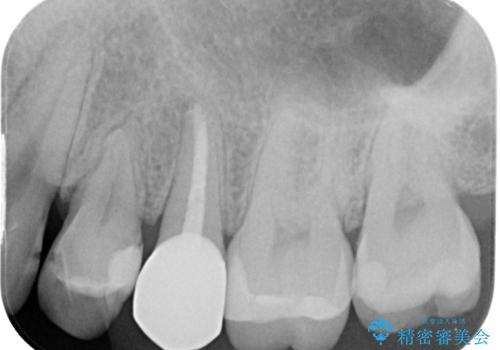

- 左上に違和感があるとのことで来院された患者様です。レントゲン撮影の結果左上の6番目の歯の近心側に虫歯を認め、フロスも引っかかる状態でしたのでセラミックインレーにて修復治療を行っていくこととしました。

拡大鏡視野下でコンポジットレジン、虫歯を除去しセラミックインレーに適した形に整えました。

歯と歯茎の間に圧排糸と言われる糸を入れてシリコーン印象材にて精密な型どりをしました。

セラミックインレーの装着時には、唾液の侵入を防ぐために、ラバーダム防湿を行いました

また、左上の4番目のメタルインレーが脱離しているところについては患者様のご希望により保険診療のコンポジットレジンにて修復しています。